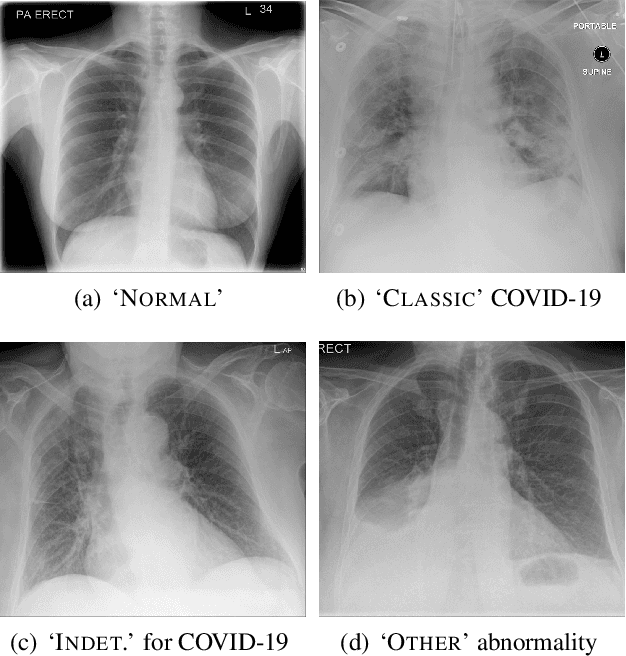

Chest radiography has been a recommended procedure for patient triaging and resource management in intensive care units (ICUs) throughout the COVID-19 pandemic. The machine learning efforts to augment this workflow have been long challenged due to deficiencies in reporting, model evaluation, and failure mode analysis. To address some of those shortcomings, we model radiological features with a human-interpretable class hierarchy that aligns with the radiological decision process. Also, we propose the use of a data-driven error analysis methodology to uncover the blind spots of our model, providing further transparency on its clinical utility. For example, our experiments show that model failures highly correlate with ICU imaging conditions and with the inherent difficulty in distinguishing certain types of radiological features. Also, our hierarchical interpretation and analysis facilitates the comparison with respect to radiologists' findings and inter-variability, which in return helps us to better assess the clinical applicability of models.